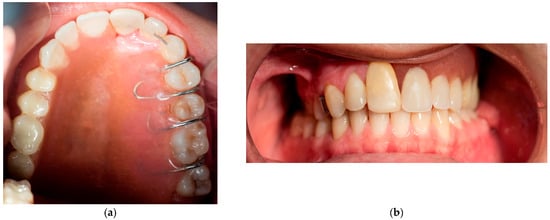

The fibroma was surgically excised. A bone graft harvested from the right scapula was placed in the defective area; however, due to the lack of vascularization, the graft was rejected. A second graft, taken from the left scapula, was also unsuccessful. Later on, a custom removable appliance was manufactured to restore function, esthetics, and facial contour of the stomatognathic system. The prosthesis on the dental cast is shown in Figure 1a, while Figure 1b shows the frontal view of the same cast. The occlusal anatomy of the edentulous defect is visualized in Figure 2a. The upper right central incisor was intruded, and a tooth extension of the removable appliance in #11 space was added. The appliance extended into the defective area, and an important feature was the hollow design of the segment extending into the sinus cavity, which contributed to increased retention while minimizing weight (Figure 2b). Over the course of time, the appliance had been periodically modified as needed to accommodate craniofacial growth and the development of neighboring structures. By October 2023, the patient had undergone orthodontic tooth movement with fixed appliances for space closure of the upper right quadrant. A panoramic radiograph was obtained, demonstrating the left-sided maxillary resection and completed orthodontic space closure, with preserved dental alignment on the contralateral side (Figure 3).

The removable appliance was designed to restore the left side of the maxillary space defect. It replaced the base of the maxilla and extended into an oval projection that partially occupied the maxillary sinus space. This projection was bordered by a shallow peripheral groove, which played a critical role in the retention of the appliance (Figure 5a). The prosthesis was further stabilized by four 0.7 mm metal ball clasps, positioned in the interproximal spaces between the canine, premolars, and molars on the contralateral side of the defect (Figure 5b). Intraoral examination confirmed proper adaptation of the appliance, as demonstrated in the occlusal (Figure 6a) and frontal intraoral views (Figure 6b).

Figure 2. (a) Occlusal photograph of dental cast without the appliance. (b) The main characteristic of the removable appliance is the internal part that exceeds the maxillary sinus, which is hollow to achieve better retention with minimal weight.